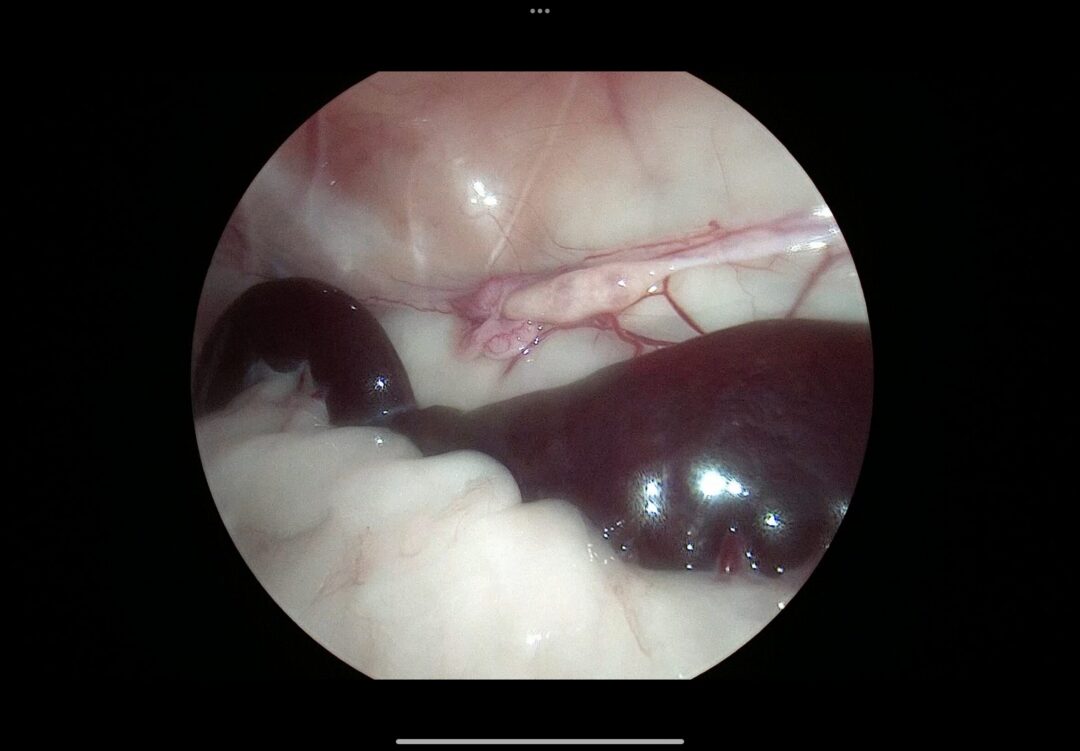

腹腔鏡下での気腹による視野の広さを生かし遺残した卵巣を摘出することにしました。

右側腎臓が無形成であったため右側からアプローチをしたところ卵巣が見つかりました。